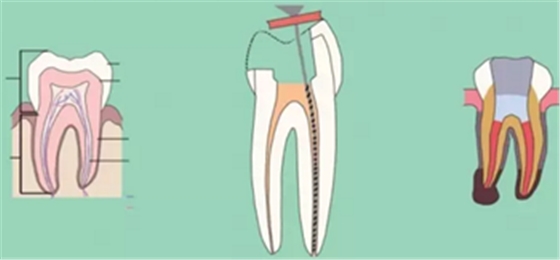

二、根管預(yù)備后形態(tài)

牙體缺損的修復(fù)需要將剩余牙體組織制備成一定形態(tài),以利修復(fù)體的良好固位。根管充填為了致密封閉根管系統(tǒng)也需要良好的根管預(yù)備后形態(tài)。

常規(guī)概念的根管預(yù)備后形態(tài)有:

( 1 )便宜形態(tài)( convenience form )

( 2 )保持形態(tài)( retention form )

( 3 )抵抗形態(tài)( resistance form )

1. 便宜形態(tài)

便宜形態(tài)是自切端或咬頜面朝向根尖的直線開擴尖錐形態(tài),減少污染物推出根尖孔,方便沖洗、根管充填和側(cè)壁施壓。

2. 保持形態(tài)

保持形態(tài)是根尖狹窄部內(nèi) 1 — 2mm 的一段距離,由擴大器回轉(zhuǎn)切割而不貼根管壁提拉切割制成,是擴大器的原始形態(tài)(近似平行)。在測試主牙膠尖時給測試者有一個牽引抵抗 (tugback) 的感覺。

3. 抵抗形態(tài)

抵抗形態(tài)是根管預(yù)備的根尖形態(tài),它是由擴大器或根管銼尖端 75 度角自然切割而成。其目的是防止根管充填材超出根尖孔,并且使根尖封閉更加嚴(yán)密。

三、開髓孔

1. 正常開髓孔的位置和大小

左圖為正常開髓孔的大小和位置。左邊圖為下顎,右邊圖為上顎。

2. 根管治療中開髓孔的設(shè)計標(biāo)準(zhǔn)

根管治療需去除髓腔內(nèi)容物(去除髓室頂),建立所有根管的入路,允許沖洗液大量沖洗。開髓孔的設(shè)計標(biāo)準(zhǔn)以建立通路為目的,從而建立良好的視野和術(shù)野。

( 1 )直線通路:根管治療時需要一個直線通路,直線通路能夠達(dá)到根尖三分之一

測量標(biāo)準(zhǔn):以允許根管器械直線并直接進(jìn)入根尖 1/3 且不接觸冠方各壁為標(biāo)準(zhǔn)。

( 2 )髓腔其他改變:如髓室頂、繼發(fā)性牙本質(zhì)、修復(fù)性或增齡性牙本質(zhì)。見左圖。

右圖中有繼發(fā)性牙本質(zhì),切削后獲得直線通路。